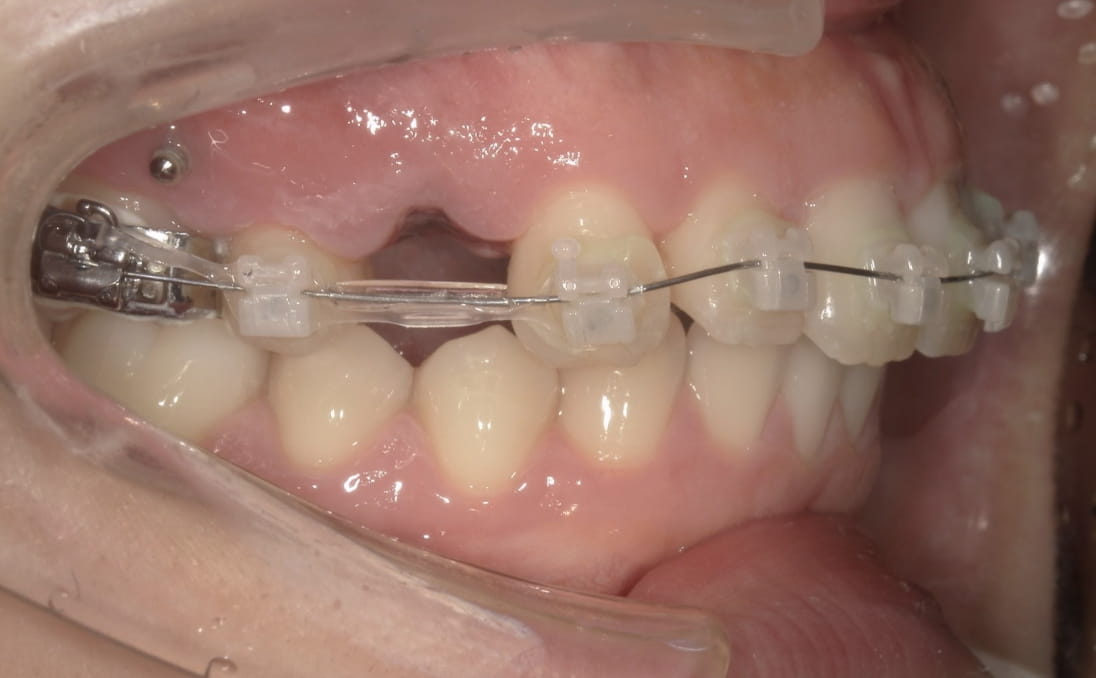

《上下顎前突》

症例63

性別:女性 年齢:20歳 お住まいの地域:奈良市

主訴 口元が出ている

治療装置 ハイブリット(白い表側矯正装置とマウスピース型矯正装置)

抜歯 抜歯

治療期間 2年9ヶ月

診断名 上下顎前突

副作用 歯肉退縮・歯根吸収・歯髄壊死・癒着による予期せぬ歯の動き

白い表側矯正装置からはじめ、上下顎4本の抜歯を行いました。抜歯スペースが1m mになった際にマウスピースに切り替えました。

治療中(3ヶ月後)